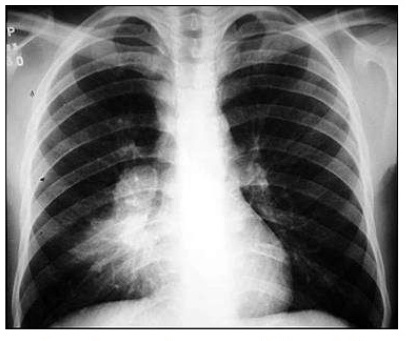

Adenomegalia hilar unilateral - pensar em…

TB PRIMÁRIA

O que é nódulo de Ghon?

Um granuloma visualizado na radiografia de tórax

Quais são as 2 formas de TB pulmonar primária?

1) Quadro típico: Crianças

2) TB miliar

Que forma de TB é esta?

TB pulmonar primária

TB em forma cavitária representa que momento da infecção?

TB PÓS-PRIMÁRIA

Paciente é BACILÍFERO